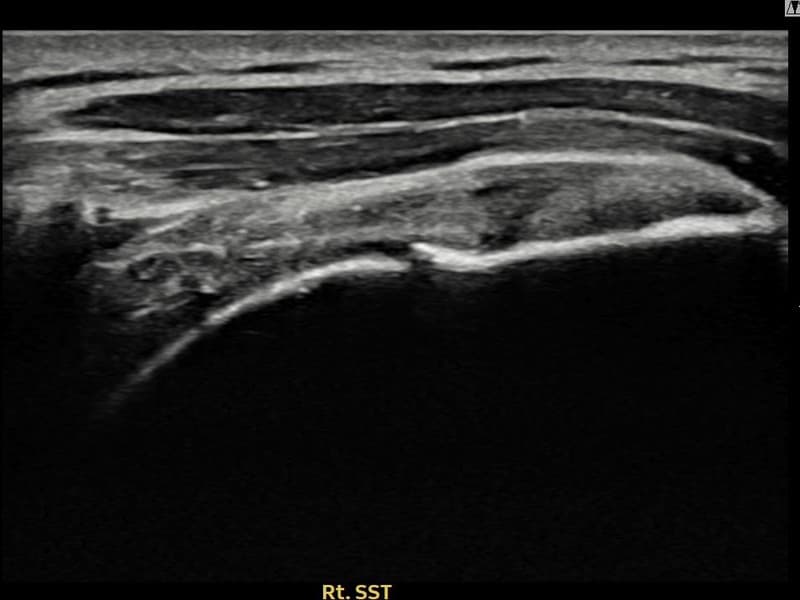

시술 전 초음파 측정 결과 파열 크기는 9mm × 4mm (힘줄 두께의 약 38% 결손)로 확인되었습니다. 시술 전 초음파에서 우측 극상근건 내 에코 단절과 함께 건내 고에코 석회화 소견이 동반 확인되었습니다. 시술 후 초음파에서 파열 부위의 연속성이 회복되고 석회화 부위의 에코 패턴이 개선된 것이 관찰되었습니다.

50대 후반 여성 환자분으로, 야간 통증이 극심하여 어깨를 아래로 향하고 자도 통증이 느껴지는 상태로 내원하셨습니다. 초음파 검사에서 극상근건 부분파열과 함께 건내 석회화가 동반된 복합 소견이 확인되었습니다. 석회화와 파열이 함께 존재하는 경우 충격파만으로는 힘줄 구조 회복이 어려워 초음파 유도 하 축소봉합술을 선택하였습니다. 시술은 30여 분에 완료되었고 당일 귀가 가능하셨으며, 이후 보조기를 착용하며 단계적 재활을 진행하였습니다. 시술 11주 후 추적 초음파에서 파열 부위 연속성 회복과 함께 석회화 소견도 뚜렷이 감소한 것이 확인되어 야간 통증 없이 정상 생활에 복귀하셨습니다.